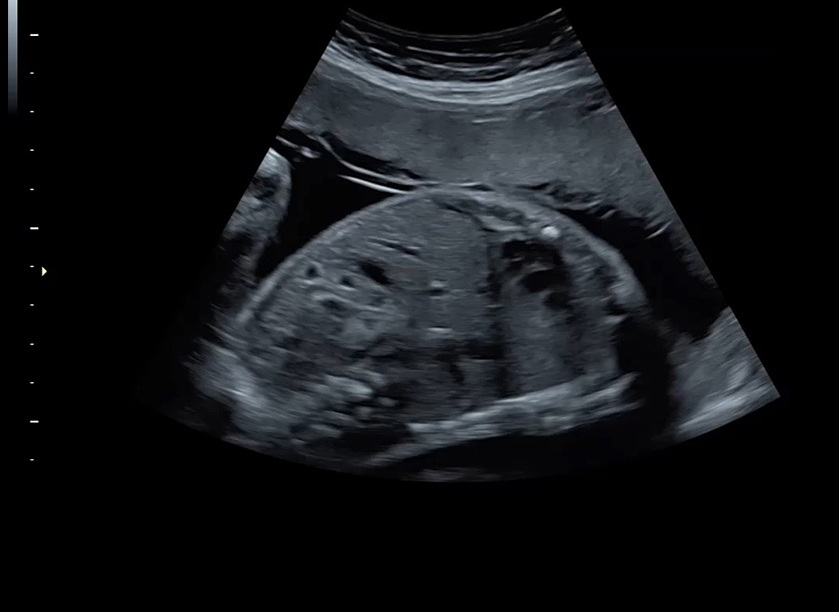

• Высокое качество изображений: Voluson S8 обеспечивает высококачественные изображения, позволяющие детально оценить состояние плода и обнаружить возможные патологии.

• Высокочувствительные датчики: Ультразвуковой сканер Voluson S8 оснащен высокочувствительными датчиками, что позволяет проводить полноценное обследование даже у пациентов с сложными анатомическими особенностями.